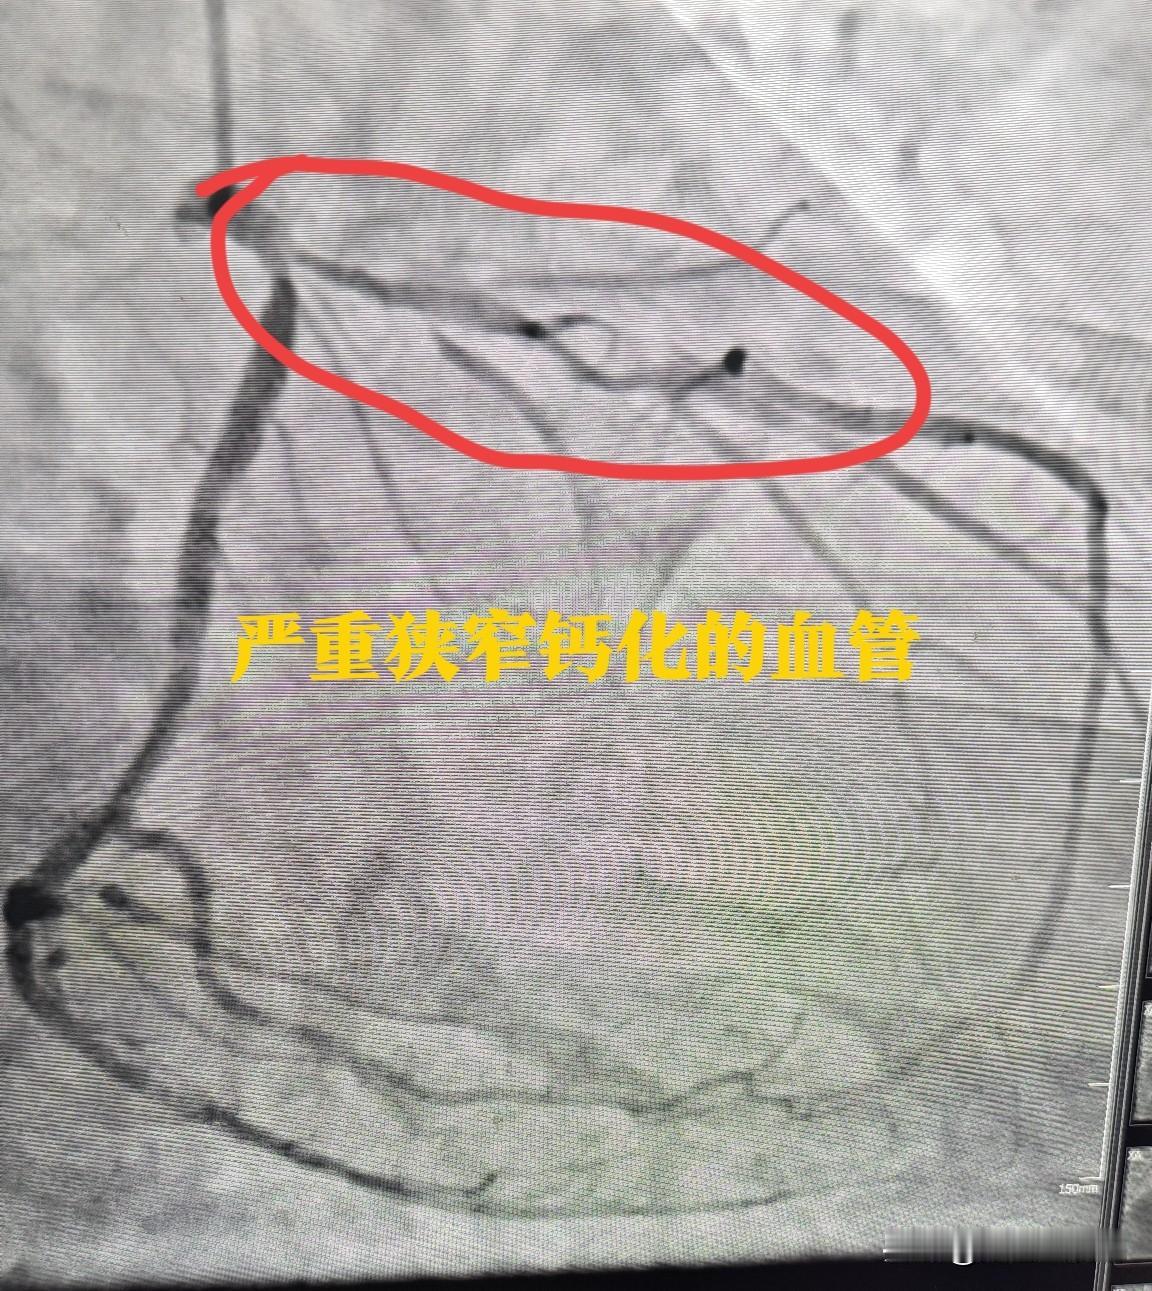

我已经装心脏支架2年了,一口气装了三个,刚出院那段时间是很小心翼翼的,酒不喝了,烟也戒了,吃的都清淡很多,但没敢运动,主要还是静养。再后来身体好了不少,网上看到那些骇人的后遗症好像也没发生,人可以正常生活。但前段时间我发现了不对,先是乏力,走不了多久就累了,走几步就想歇脚。我听我几个朋友说,心脏支架毕竟是异物,放到体内肯定会有症状反应的,还有说这是支架过期了,越想越焦虑,这几天感觉很心慌,心跳会加快,有点担心,这到底是怎么回事?是支架的问题吗? 医生回复:装心脏支架2年后出现乏力、心慌,不一定是支架问题。支架使用寿命通常10-15年,且您术后恢复良好,过期可能性小。乏力可能与心脏功能未完全恢复、贫血、心理因素或未规律康复有关;心慌可能由精神紧张、心脏负荷加重或心肌缺血引起。建议及时就医,通过心电图、心脏超声等检查明确原因,再针对性治疗,避免焦虑加重症状。